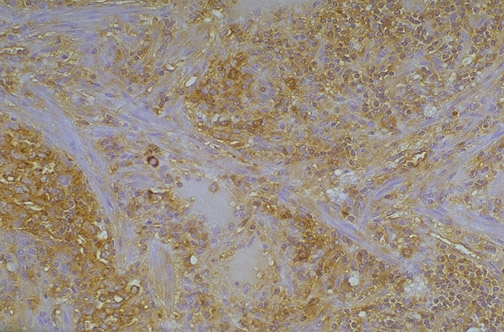

This section of normal liver demonstrates staining of hepatocytes for alpha-1-antitrypsin.